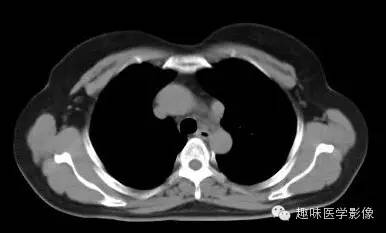

两肺未见明显异常。纵隔左侧见血管影,经主动脉弓与左肺肺门之前向下走行,汇入冠状静脉窦。

永存左上腔静脉